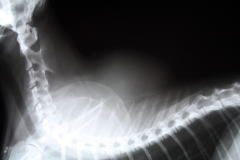

�f�@�̌��ʁA�����g�Q���B�e�Ɛj�����i�V�R���̈ꕔ�ɐj���h���Ăǂ�ȍזE�ō\������Ă��邩���錟���ł��B�j���s���܂����B

�ȉ������g�Q���ʐ^�ł��B

�����g�Q�������@���t���Ϗk�A�S���́A��≡�ɌX���Ă���i����ׁ̈j�@���ł̞��ˋN�ɍ��Z��a�ρi�V�R���̉��̔w���Ɏ�ᇂ��L�����Ă��鎖���Ӗ����܂��B�j�A���b������i��p���A����ł̊m�F���K�v�ł��B�j

��p�O�̎�ᇂ̎ʐ^�ƃ����g�Q���ʐ^�ł��B

�ȉ������g�Q���ʐ^�ł��B

����Ȏʐ^�ł��B

����ȓ�{�̍�������ł��܂��B

�V�R���̂��鑫�ł��B

��{�̍��̉E���ɑȉ~�`�̔����݂���Ǝv���܂��B���Ȃ�A�傫���ł��B�����̌��ʂ́A�얞�זE��i������ᇁj�Ƃ������̂ł����B